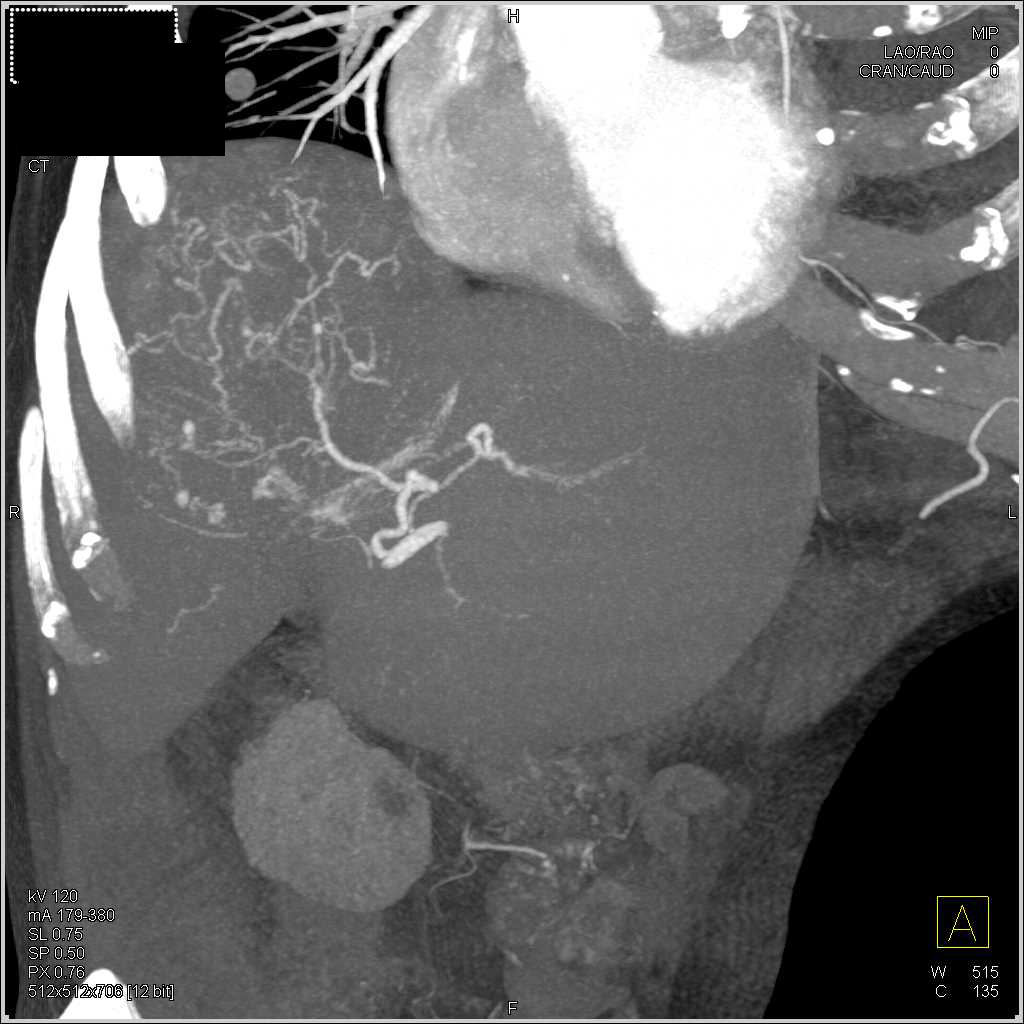

Wall Stent in Common Bile Duct